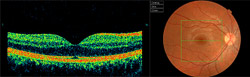

La tomografía de coherencia óptica (OCT) es una técnica que evalúa mediante imágenes las capas de la retina, visualizándose un corte transversal de la zona de la retina deseada. Ante la más mínima alteración entre capas (como en los casos de DMAE) y gracias a las diferentes prespectivas visuales que ofrece su software, cualquier alteración quedará proyectada, medida, comparada y monitorizada. Permite incluso la obtención en 3D de la retina evaluada.

Cuenta con una base de datos (estudios de población), que compara automáticamente el espesor de las fibras ganglionares del la retina que se dirigen al nervio óptico para valorar su rango de normalidad. Muy útil en el caso de pacientes con glaucoma, tanto como apoyo en diagnóstico como en su seguimiento en futuras revisiones.